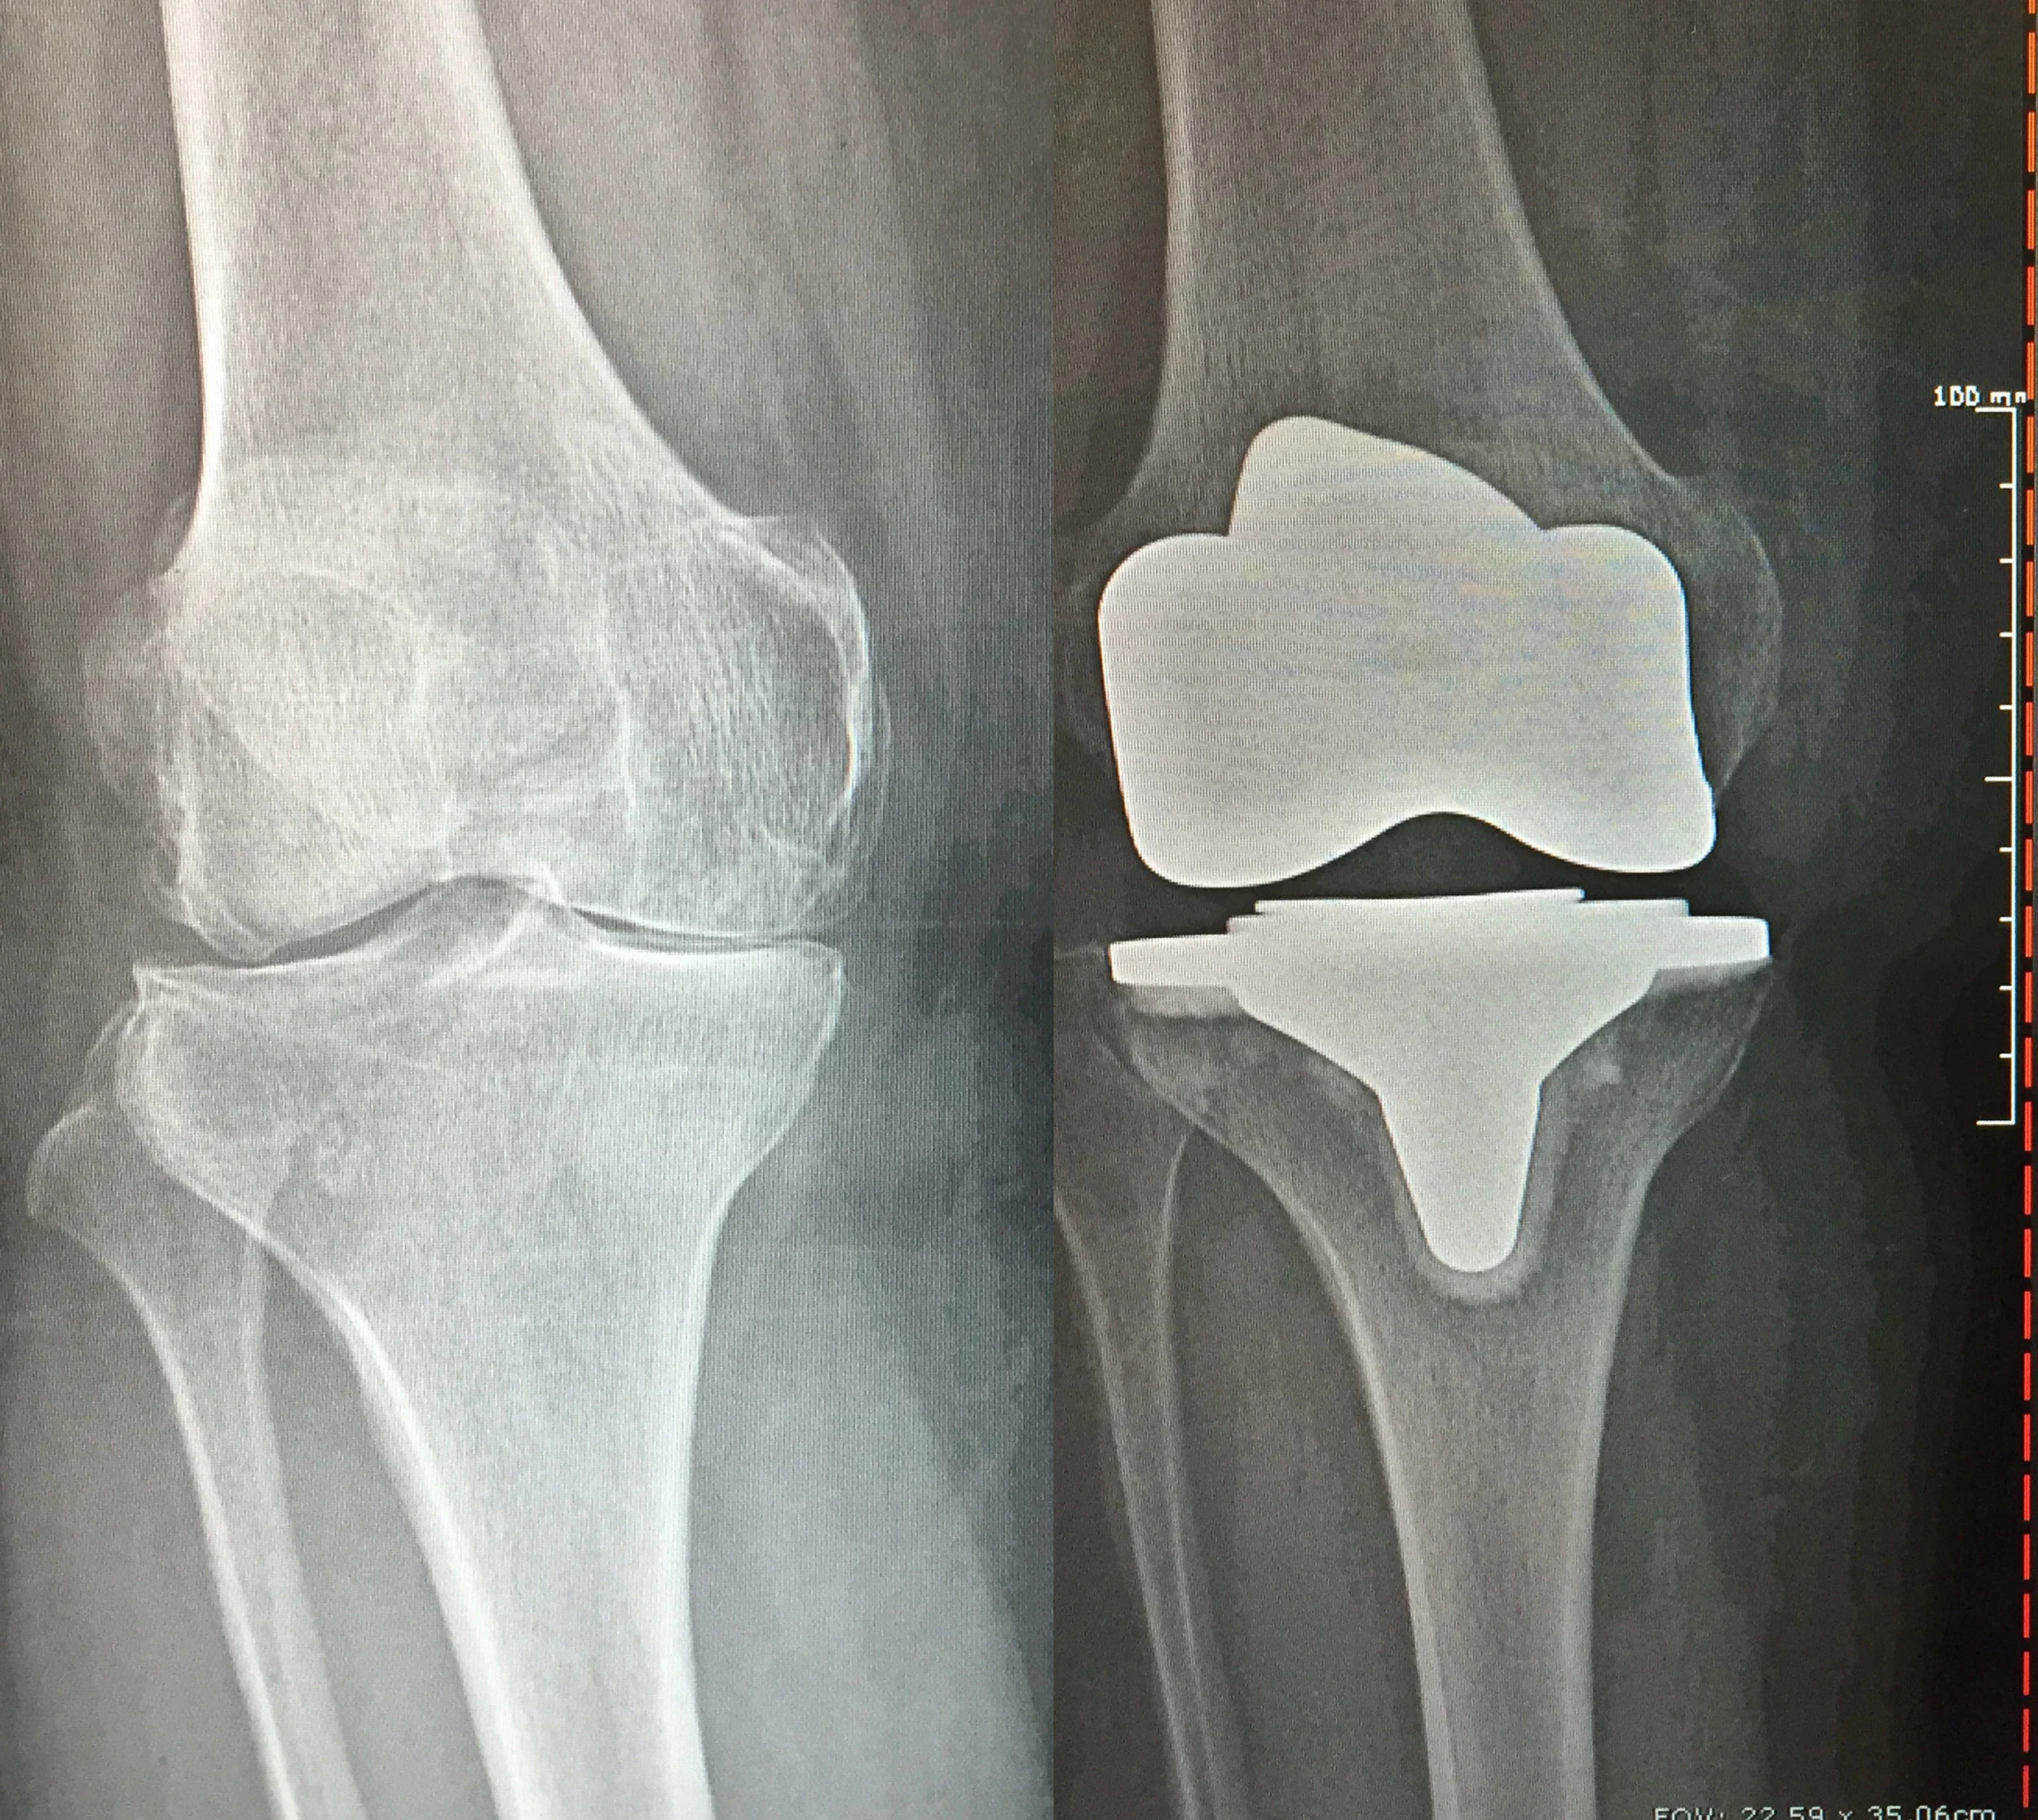

Before and After Knee X-Rays

Before: Bone on bone knee arthritis

After: Total Knee Replacement

BIOMET

Before: Bone on bone spurs

After: Total Knee Replacement on 59 y/o female

DEPUY